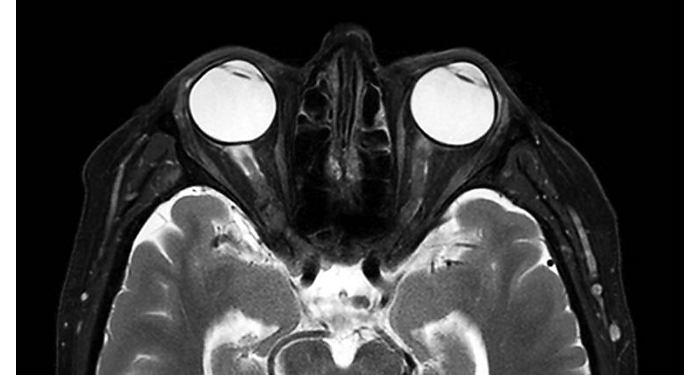

70% of radiologists consider neuro indications to be challenging, mostly due to a lack of appropriate imaging and visualization techniques¹. Philips aims to provide the best possible diagnostic clarity and treatment guidance for all patients with neurological disorders. By leveraging our dStream digital platform, this year, we are introducing, a set of novel imaging and visualization strategies. These may empower you to resolve complex neuro questions with more certainty, as well as unlock new neuro territories in advanced Neurofunctional applications. This is a key step towards elevating neuro diagnostics and ultimately touching more lives with MR imaging. ¹ TMTG Market Survey 2016

New neuro applications